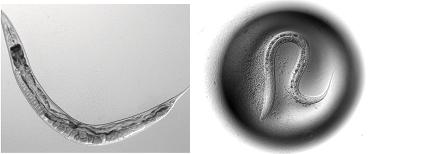

BETHESDA, MD - A new screening approach uses several types of roundworms to identify chemicals that might one day help people stay healthy longer. Researchers will present initial findings from their search for anti-aging compounds at The Allied Genetics Conference, a meeting hosted by the Genetics Society of America.

Researchers from the Buck Institute are working with teams led by Patrick Phillip, Ph.D., at the University of Oregon, and Monica Driscoll, Ph.D., at Rutgers University, in a consortium called the Caenorhabditis Intervention Testing Program (CITP), which is funded by the National Institute on Aging. Consortium researchers are using multiple species and strains of the roundworm Caenorhabditis to identify chemical agents that can delay the effects of aging across multiple organisms from diverse genetic backgrounds.

The processes involved in aging are quite complex and are likely influenced by a person's genes. The idea behind CITP is that if scientists can find agents that show effects in organisms with diverse genetic backgrounds, those agents might be more likely to be effective in humans, as well. Since roundworms live only about three weeks, they can be used to screen for chemicals affecting lifespan in a short amount of time.

The Buck Institute researchers used three strains each of the roundworms C. elegans and C. briggsae to test a panel of ten compounds that had previously shown increased longevity in C. elegans or other organisms. "For the chemicals that had been previously studied, most had been shown to expand lifespan in the laboratory adapted N2 strain of C. elegans , so we did not know what they would do in wild strains of C. elegans or in C. briggsae ," said Lucanic.